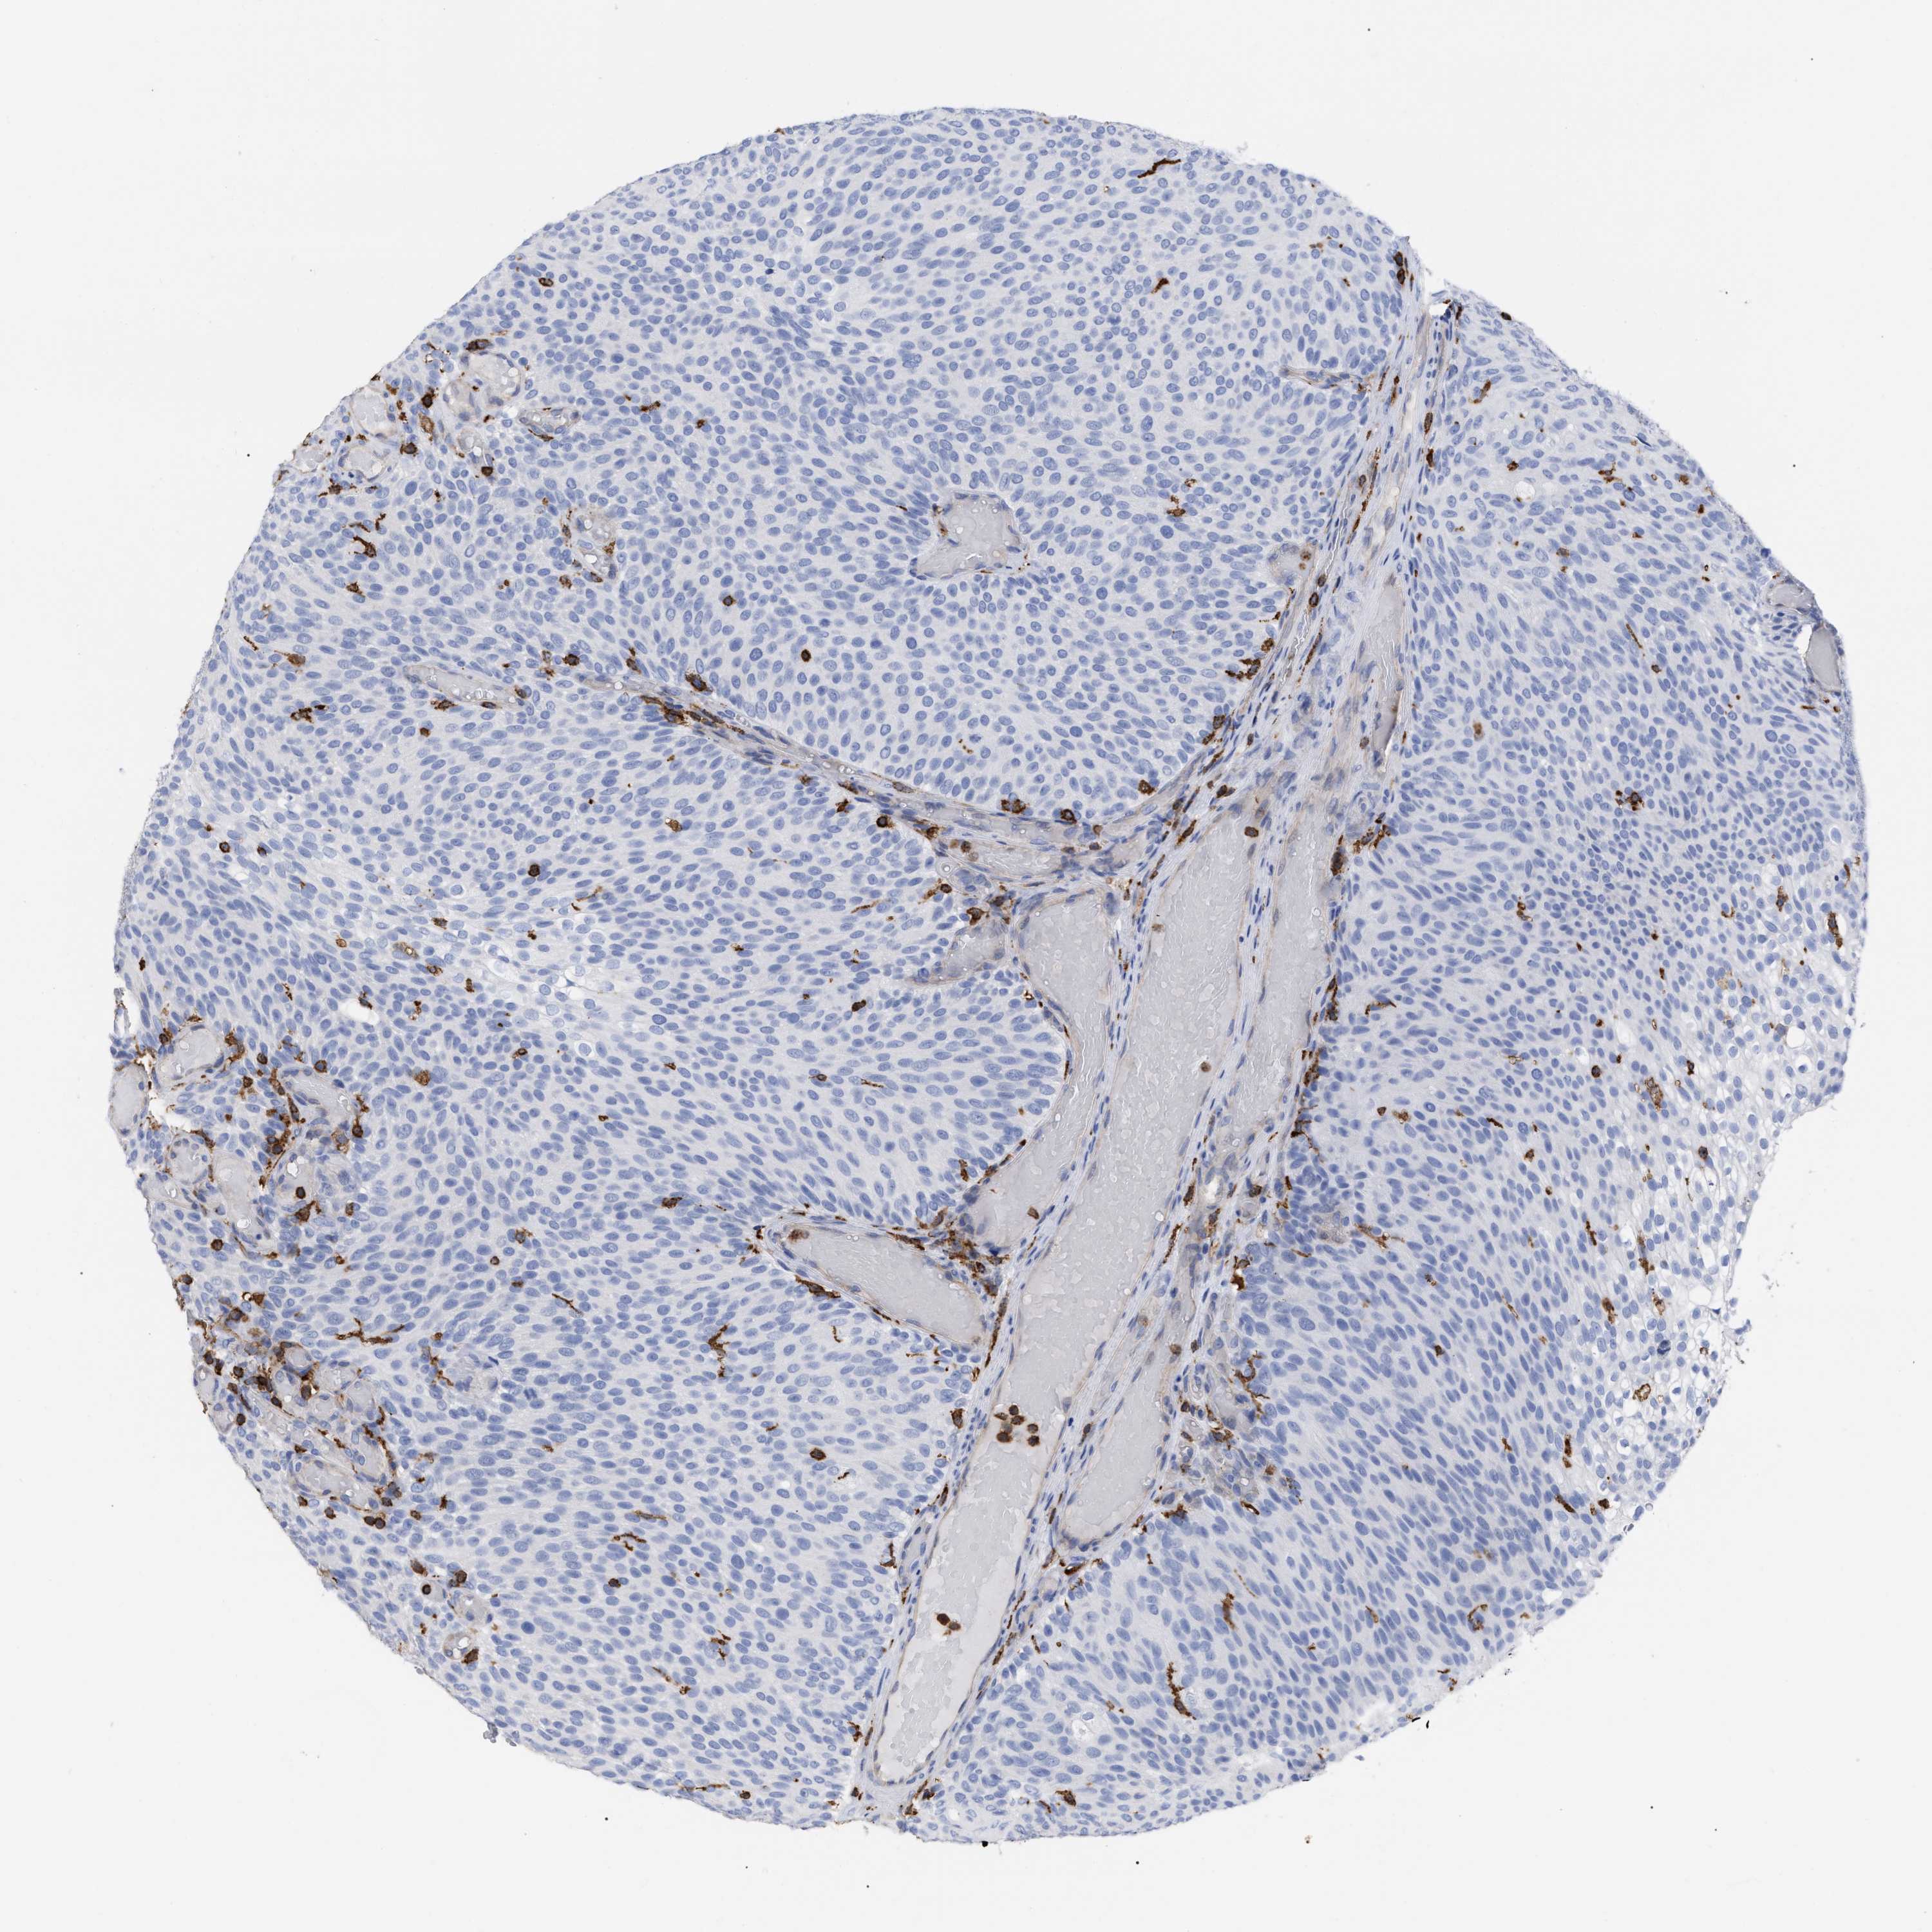

UROTHELIAL CANCER - Protein expressioni

A mouse-over function shows sample information and annotation data. Click on an image to view it in a full screen mode. Samples can be filtered based on level of antibody staining by selecting one or several of the following categories: high, medium, low and not detected. The assay and annotation is described here.

Antibody stainingi

Antibody staining in the annotated cell types in the current human tissue is reported as not detected, low, medium, or high, based on conventional immunohistochemistry profiling in selected tissues. This score is based on the combination of the staining intensity and fraction of stained cells.

Each image is clickable and will lead to virtual microscopy that enables deeper exploration of all samples and also displays staining intensity scores, fraction scores and subcellular localization as well as patient and tissue information for each sample.

Antibody HPA019143

Staining

High

Medium

Low

Not detected

Intensity

Strong

Moderate

Weak

Negative

Quantity

>75%

75%-25%

<25%

None

Location

Nuclear

Cytoplasmic/membranous

Cytoplasmic/membranous,nuclear

Urothelial carcinoma, Low grade

Urothelial carcinoma, High grade